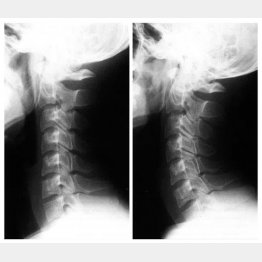

写真は男性のレントゲン画像で、左は初診時。なるほど、首の骨がまっすぐに連なっていて、ストレートネックになっている。右は、8週間の入院治療を終えて不調がすべてなくなったときのレントゲン画像で、あご側にゆるやかに湾曲しているのが確認できる。

「首の骨は、アルファベットの『C』のように前弯しているのが正常です。このカーブがあることで、5~6キロの頭の重さがうまく吸収され、首への負担を軽減できます。ストレートネックだと、その頭重がダイレクトに首にかかるため、自律神経への負担も強い。そういう生活を続けていると、男性のように肉体的な不調も精神的な不調も少しずつ広がっていくのです」